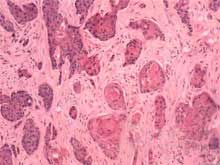

陰囊鱗癌的病理組織學改變與身體其他部位鱗癌相似腫瘤由侵入真皮內的鱗狀上皮細胞不規則增生團塊所組成。團塊內為不同分化程度的細胞但僅從鏡下觀察異形性不一定明顯,確診癌變與惡性程度仍以浸潤情況為主。根據分化及組織浸潤深度通常將陰囊鱗癌分為Ⅰ~Ⅳ級,癌腫浸潤以皮膚為主,很少侵犯到陰囊內容物。

癌巢活組織檢查:鏡下可見增生的上皮突破基膜向深層浸潤形成不規則條索形癌巢。分化好的癌巢中,有相當於基底層的細胞排列在癌巢的外層,其內為相當於棘細胞層的細胞,細胞間可見細胞間橋,癌巢的中央可出現層狀的角化物,稱為角珠或癌珠。分化差的癌巢中無角化珠形成,甚至也無細胞間橋。